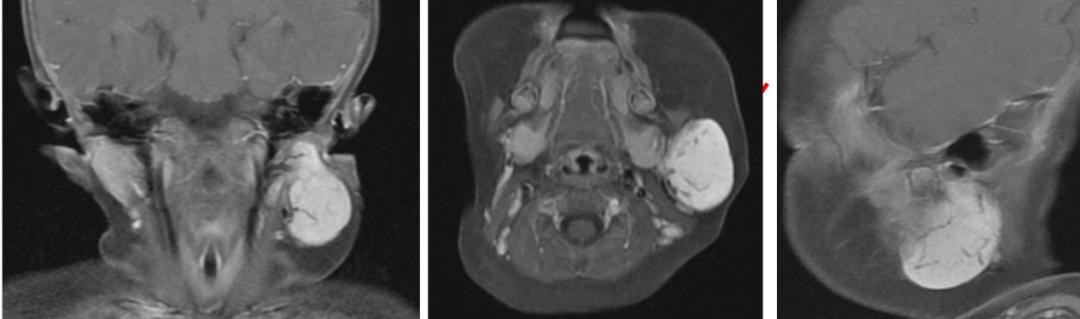

经磁共振检查,医生发现,小柚子左侧脸颊有颗直径达4厘米的肿瘤,它紧贴着控制笑容、眨眼、嘟嘴等动作的第七对神经——面神经。

磁共振提示肿物与面神经关系密切